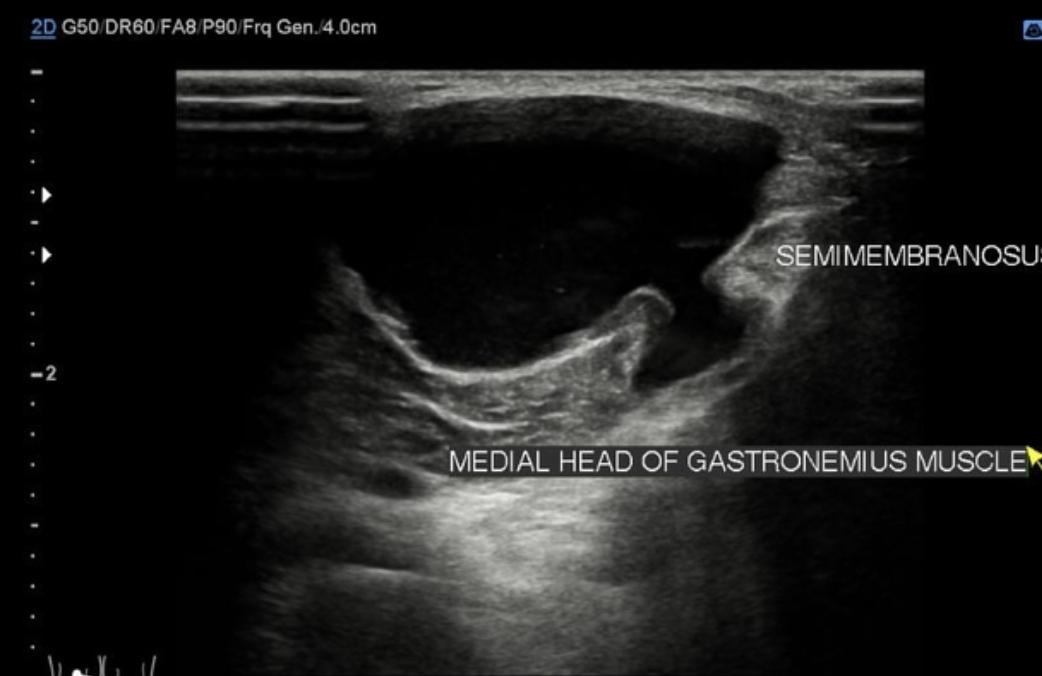

또 하나는 베이커 낭종(Baker’s cyst)입니다.

베이커 낭종은 관절 안의 활액이 뒤쪽으로 밀려 물혹처럼 만져지거나 뻐근함을 유발합니다. 오래 앉아 있거나 많이 걸은 뒤 더 불편해지는 특징이 있습니다. 겉에서 만져지지 않는 작은 낭종은 엑스레이로는 확인되지 않고 초음파나 자기공명영상(MRI, magnetic resonance imaging)이 필요합니다.

현재 양상만 보면 급성 위험 신호는 없어 보이나, 반복 재발이라면 초음파 검사를 통해 낭종 여부 확인이 가장 현실적인 접근입니다.